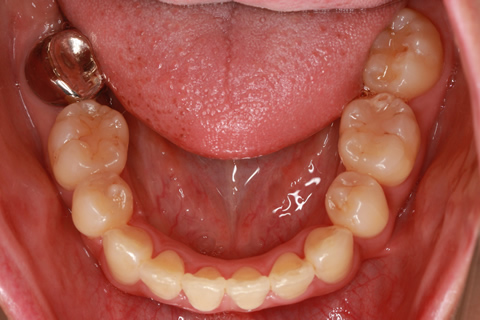

症例

治療前

治療中

治療後

- 年齢・性別

- 30歳女性

- 治療期間

- 3年0ヶ月

- 抜歯

- 上下左右4番抜歯

- 治療費

- 110万円

- 備考

- マルチブラケットを用いた矯正治療

- 治療内容

- 上下顎前突を4本抜歯にて矯正治療

- 施術の副作用(リスク)

- 表側矯正と比較して、歯根の角度を確立する「トルク」の力がかかりにくい。